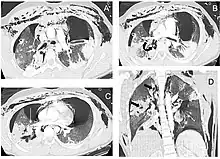

A patient with traumatic complete disruption of the right bronchus. Computed tomography scan following emergency chest tube drainage. Axial 1.25 mm thick sections with a lung window. (a) Persistent bilateral pneumothorax, pneumomediastinum and extensive subcutaneous emphysema. (b) Multiple lucencies around the right bronchial tree (curved arrow) precluding the correct recognition of the bronchial rupture. (c) The Macklin effect around the right lower pulmonary vein (white arrow). (d) Coronal view demonstrating multiple areas of alveolar consolidation in the right upper and lower lobes: intraparenchymal lucencies resulting from lung lacerations are visible on the right side (thick arrows).